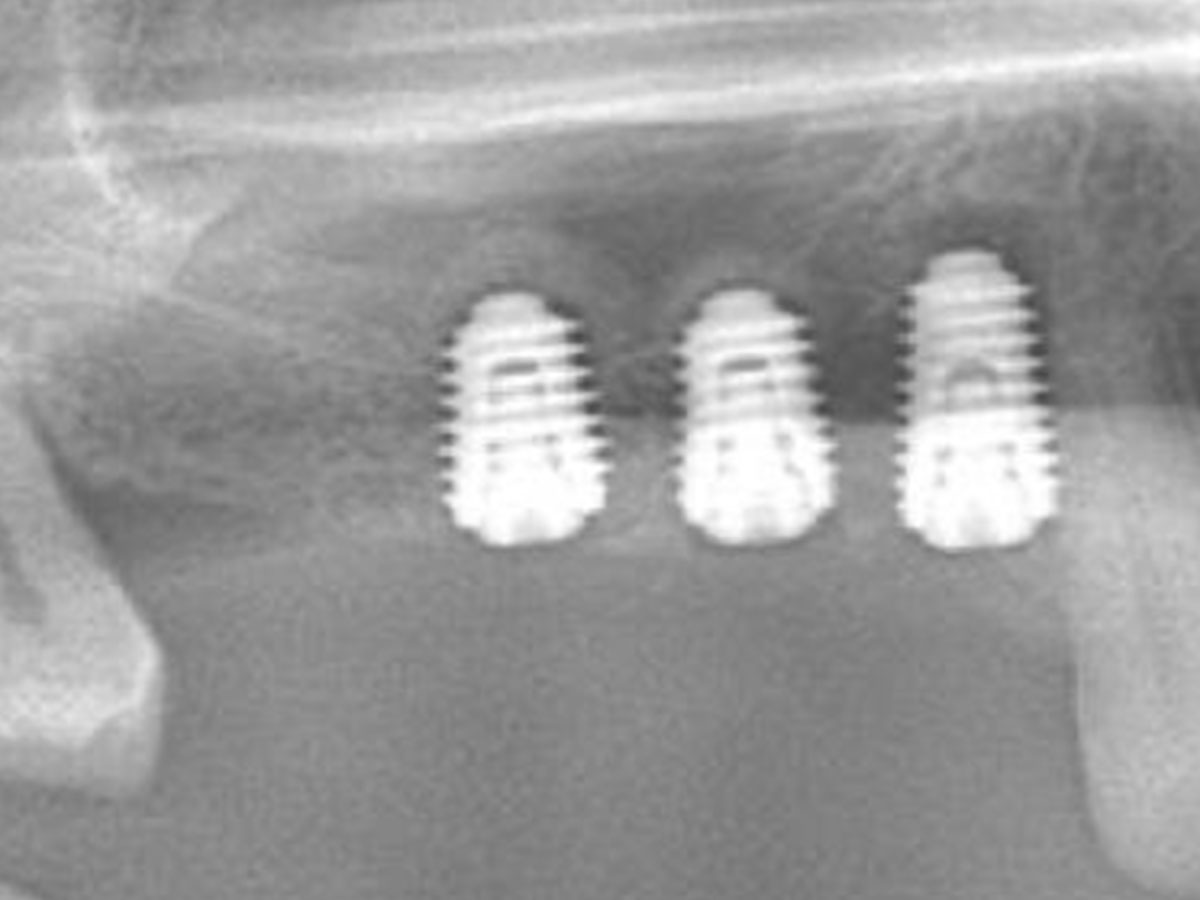

Vorhersagbare Augmentation und Knochenkondensation

· Biologische Grundlagen der Knochenverdichtung mit Densah-Bohrern (Osseodensification): Prinzip, Anwendung und Vorteile

· Indikationen bei geringem Knochenangebot und Sinusnähe

· Integration von Augmentation und navigierter Implantation im selben Workflow